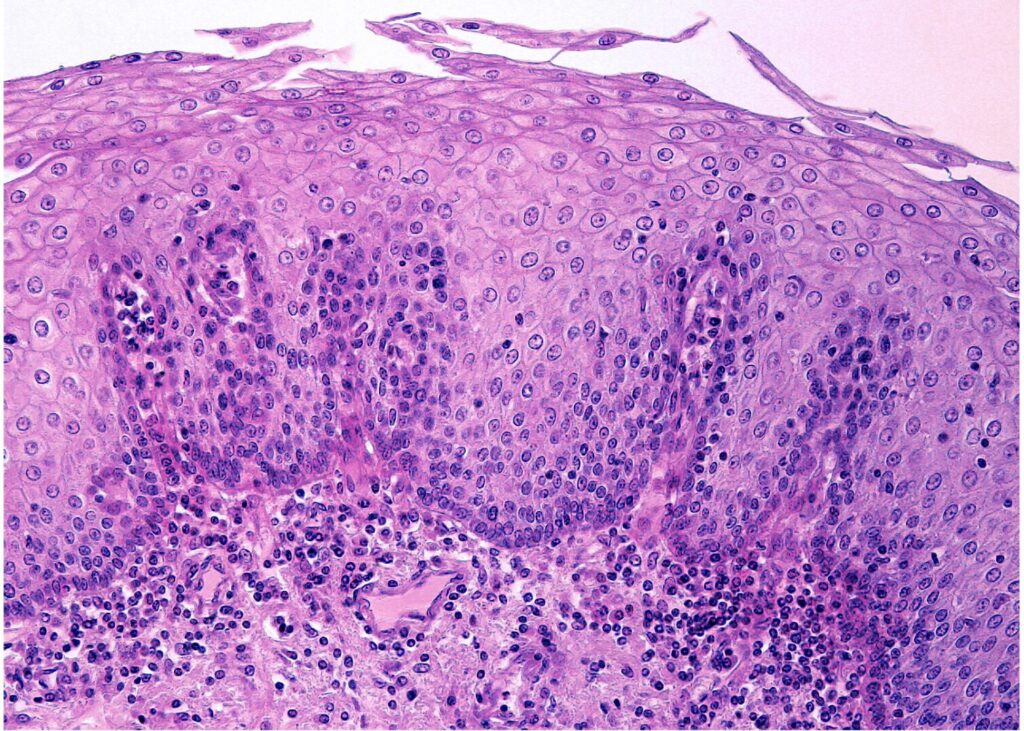

食道の粘膜上皮

食道の粘膜上皮は非角化型重層扁平上皮で被覆され、細胞間橋も明瞭にみられます。

角化と非角化は画像を見て分かるようにしておこう!

食道の次の器官は胃ですが、胃の上皮は単層円柱上皮なので、食道下端部で急に切り替わります。

また、グリコーゲンが多く含まれるため、下画像のようにPAS反応に陽性を示します。

グリコーゲンであるため、ジアスターゼ消化で陰性化します。